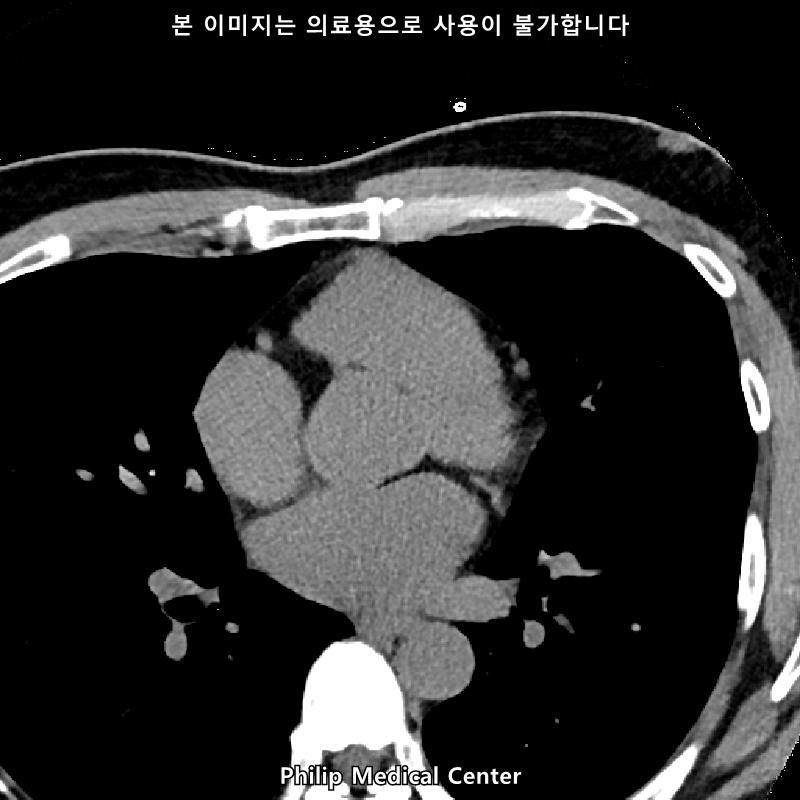

• 3번 째 사진

• 올리신 사진들을 통해서는 폐를 평가할 수 없습니다.

우측 폐첨부에 경미한 섬유성변화와 우중엽에 약 3mm크기의 결절이라는 것은 이상 소견이긴 하지만 보통 경과관찰을 하는 소견입니다.